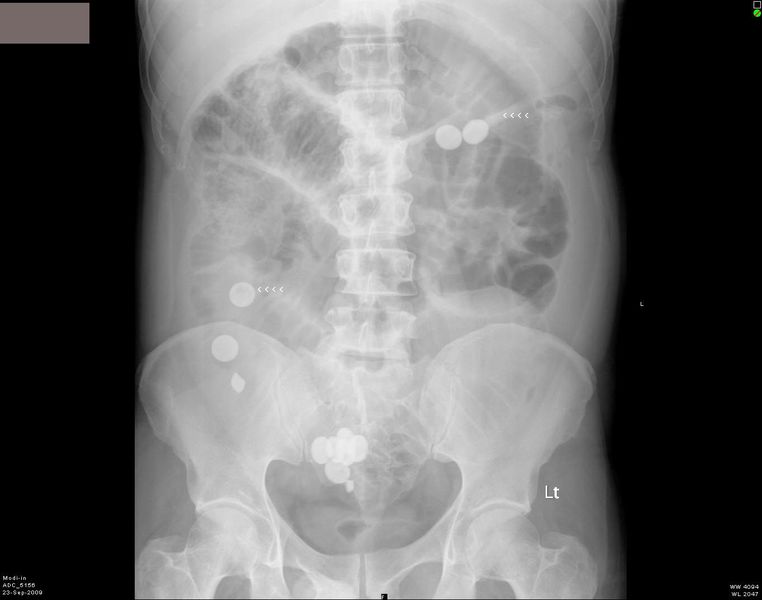

This patient presented with abdominal pain and distension of abdomen. Plain X-ray abdomen show multiple radio-opaque objects in the stomach and small intestine. These x-ray appearances are consistent with foreign bodies (pills) in the GI tract. The patient had a history of taking tablets (pills) orally just before the X-rays. There is also evidence of intestinal obstruction. Note the gas distended small bowel and air fluid levels. Both images are courtesy of Shlomo Gobi, Israel.